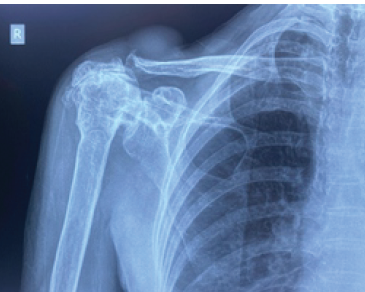

Bipolar Clavicle Fracture in Elderly: A Rare Case Report

A S Arun Kumar , B Bidhu , G Ranjit Kumar , Vishnu Harikrishnan

………………………………p.58-62